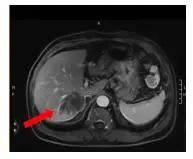

腹部增强MRI:胃壁增厚并腹腔内多发肿大淋巴结(较大者直径约2.6cm),考虑胃Ca并淋巴结转移;肝内多发异常信号灶,考虑转移瘤,6.4*7.8cm。

图1 腹部增强MRI